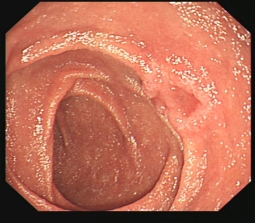

早期胃癌及内镜手术

消化道早癌的病例展示(经内镜手术或活检证实):

胃角的腺癌

胃窦的微小腺癌

胃窦印戒细胞癌

十二指肠降段早癌

胃窦的腺癌 行ESD治疗